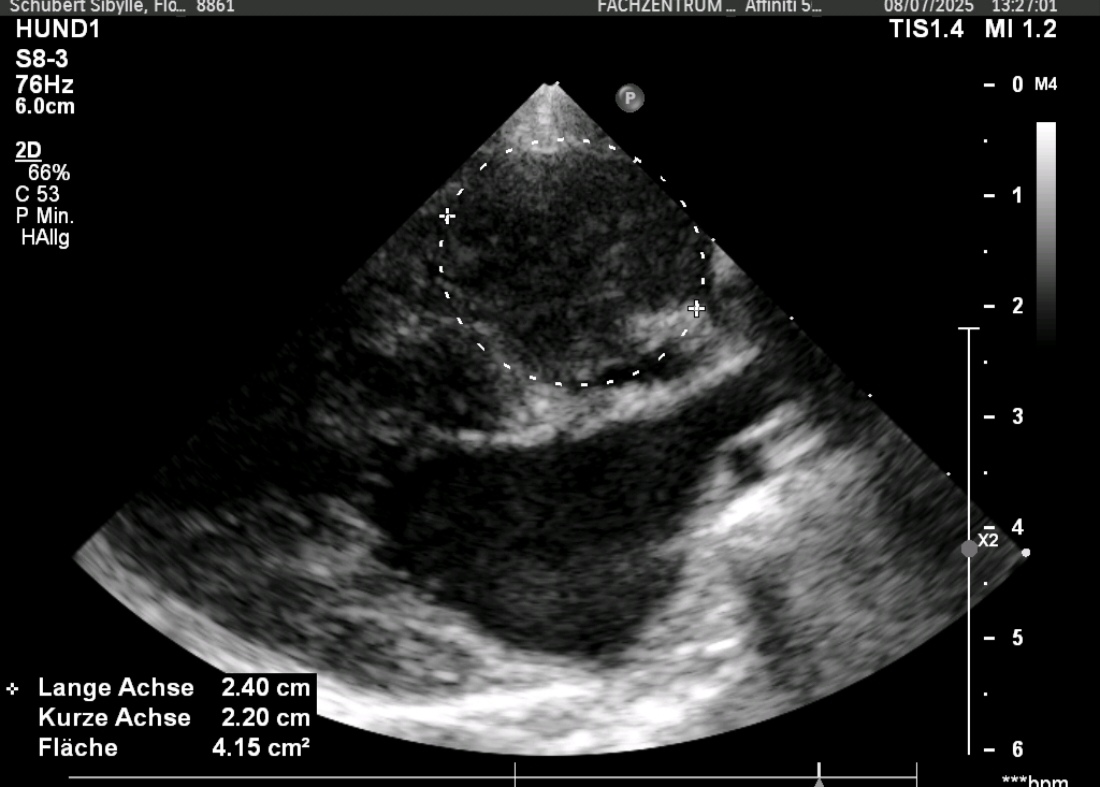

Chihuahua „Peppi“ sollte vor einer anstehenden Zahnsanierung noch mal seine bekannte Mitralendokadiose, sprich Herzklappenerkrankung, gecheckt bekommen. Doch was Frau Dr. Eulitz entdeckte, hatte leider mit dem Vorbefund nichts mehr zu tun. In Peppis rechtem Herzen war ein Tumor gewachsen. Obwohl dieser die rechten Herzanteile deutlich komprimierte und sogar ein leichter Perikarderguss vorlag, war Peppi für seine 13Jahre erstaunlich fit.